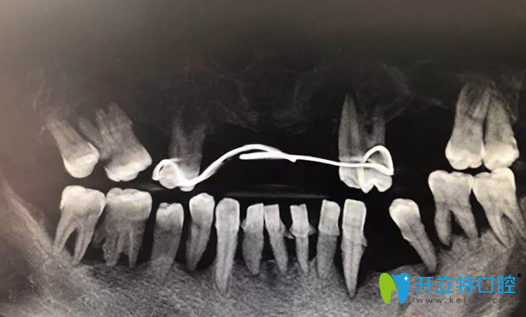

種植修復(fù)前CBCT影像:

重慶牙博士種植修復(fù)前CBCT影像